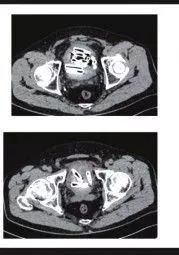

根据陆媒报导,医师透过X光照发现老翁膀胱里有许多「异物」,多次追问下,老翁这才坦承他为了寻求快感,1星期前把塑料管、生芋头从尿道塞进去。

收治患者的医师表示,原本他准备把膀胱镜放入尿道,再用夹子把异物取出来,但由于塑料管实在太粗了,无法顺利取出,最后只能把老翁推进手术室,开刀把24节塑料管、23条生芋头拉出来。

医师透露,这些塑料管、生芋头几乎都跟手指差不多粗,加起来约有200厘米这么长。